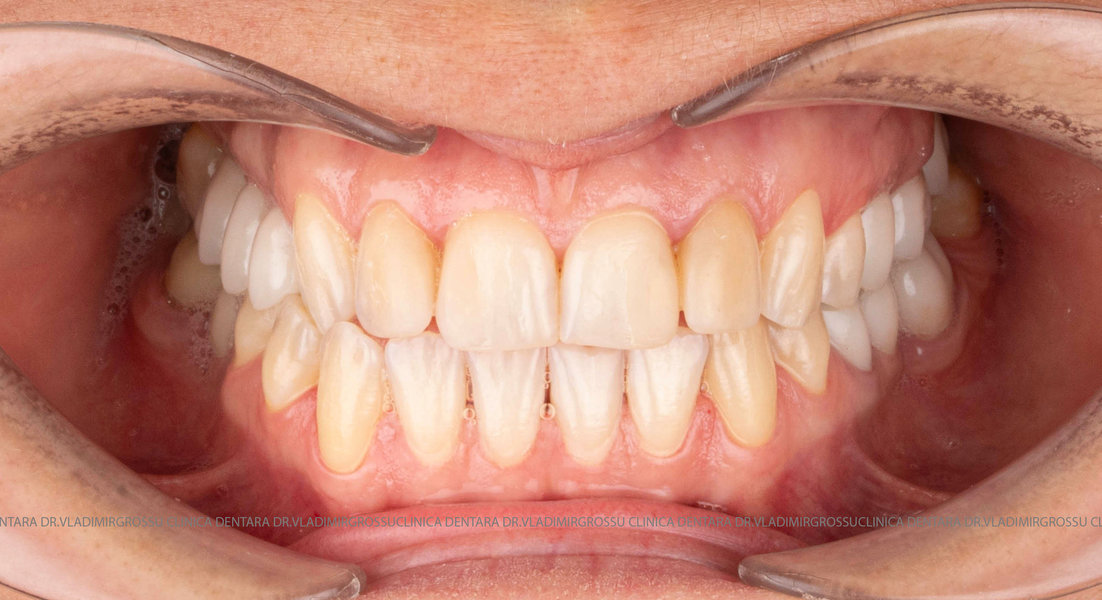

Caz 1

Transformările estetice și impactul reabilitării asupra vieții pacienților

Reabilitarea dentară produce o schimbare vizibilă și profundă în aspectul pacientului, cu efecte pozitive evidente asupra stimei de sine și a calității vieții. Mulți pacienți relatează bucuria redobândirii funcției masticatorii și dispariția complexelor legate de aspectul dentar.